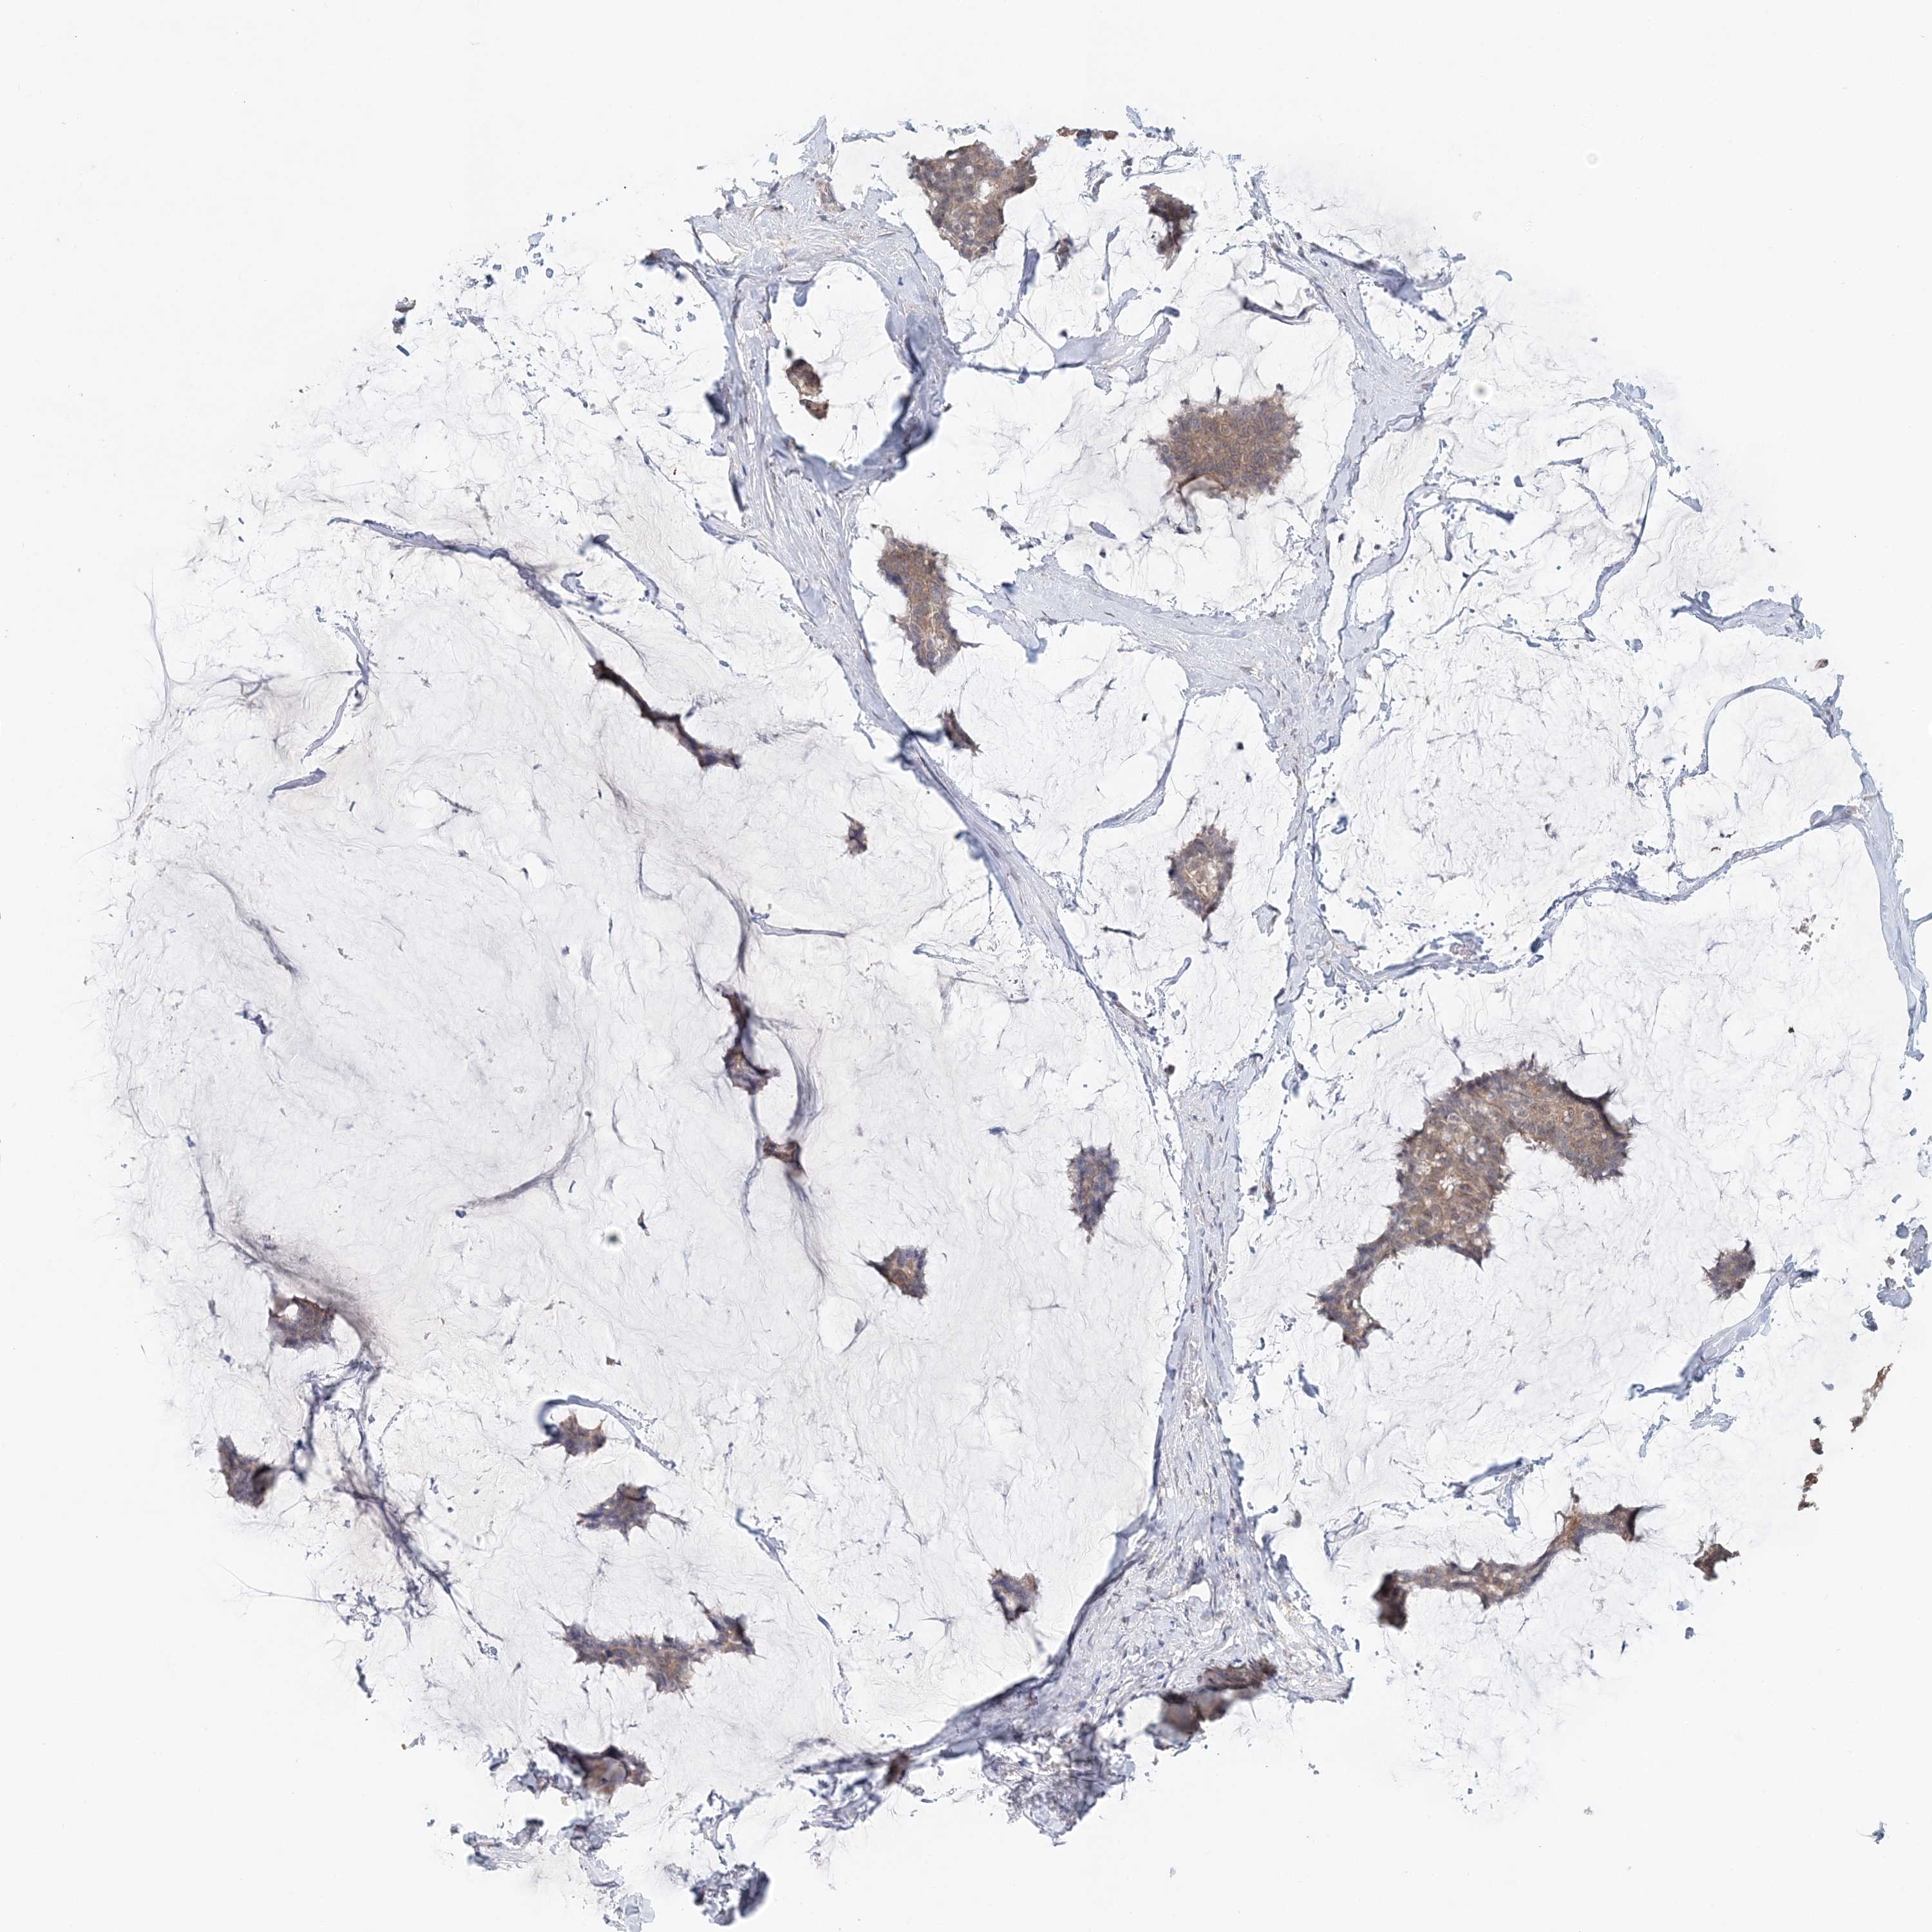

CANCER BREAST CANCER Show tissue menu

BRCA TCGA BRCA VALIDATION PROTEIN EXPRESSION

Breast cancer

Human cancer